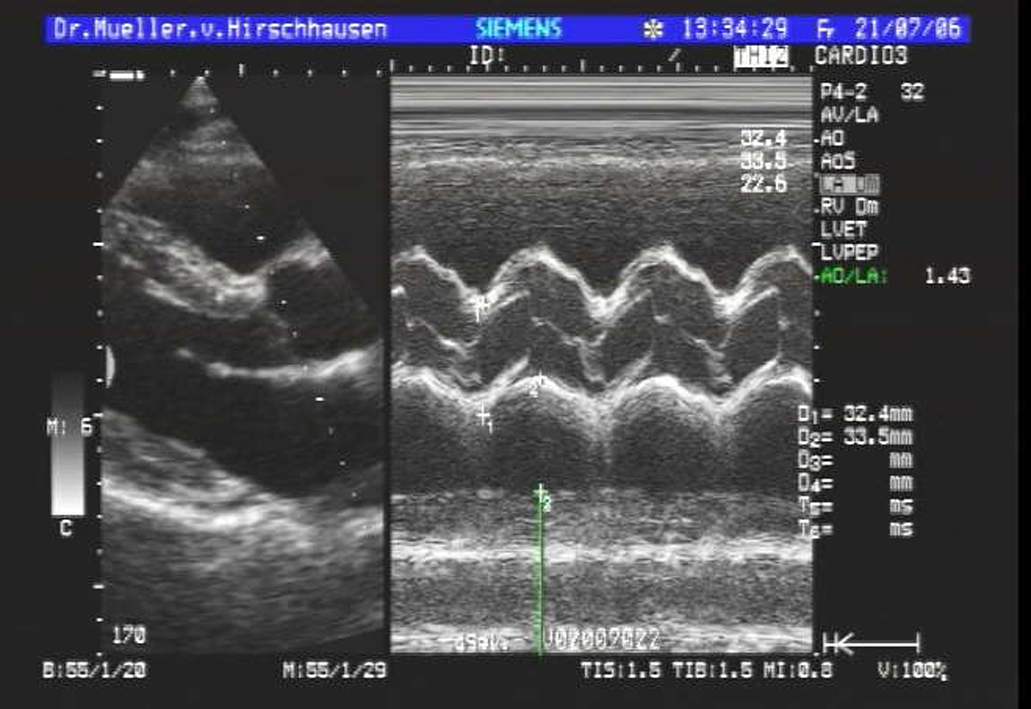

| Herz | |

Dazu kommen neben dem üblichen schwarz-weiß Bild auch moderne Verfahren zum Einsatz wie Farbdopplersonographie und Kontrastmittelsonographie der Leber.